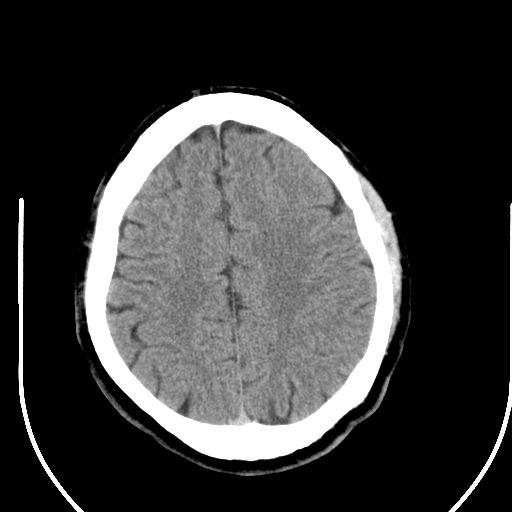

标题: CT25423:头部外伤意外发现右顶叶??? [打印本页]

标题: CT25423:头部外伤意外发现右顶叶???

ct值约13hu。

右顶叶低密度影考虑脑沟

边缘清晰,没有占位效应,不像脑沟,结合ct值,软化灶可能吧

与脑沟没关系,小软化灶或陈旧性感染吧!

看样年纪不小了直接报腔梗,当然你要想报软化灶也是一样的

考虑右侧额叶巨腔隙灶;建议必要时行mri检查。